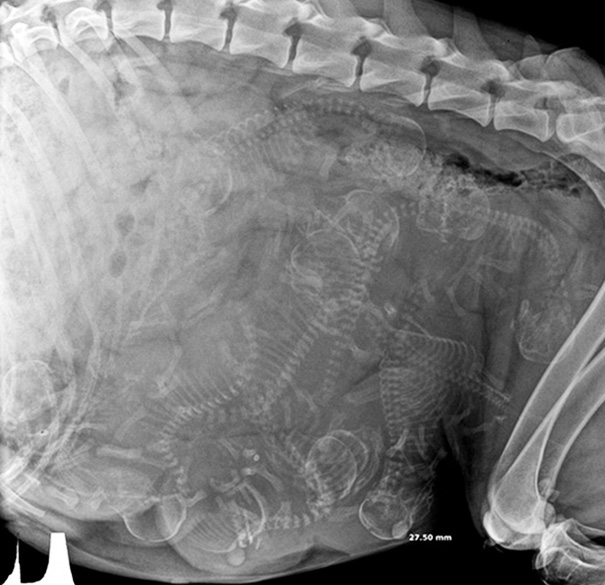

Pregnant Dog X-Ray

These are easier to see then the preg kitten. Looks like a lot of pups in there!

I hope I can't count. There's more puppies then she'll have teats to feed them.

X-Ray Of A Pregnant Dog

An X-Ray Of My Aunt's Pregnant Cocker Spaniel

X-rays are done before the due date to check position of babies and count the number of babies. However is it possible to miscount the babies. Babe, my mom's dog, was bred due to the rarity of her coat color. Everybody prepared for 8-10 puppies. Babe delivered 13 puppies.